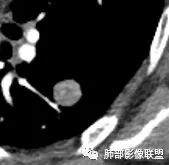

CT值46H

增强67HU

动脉期弱一些,后期强化明显一些

动脉期边缘斑点状、结节状强化为主

后期趋向于均匀强化

动脉期测量区域——中央,不是强化区域

其实强化还算是中度,幅度超过20HU